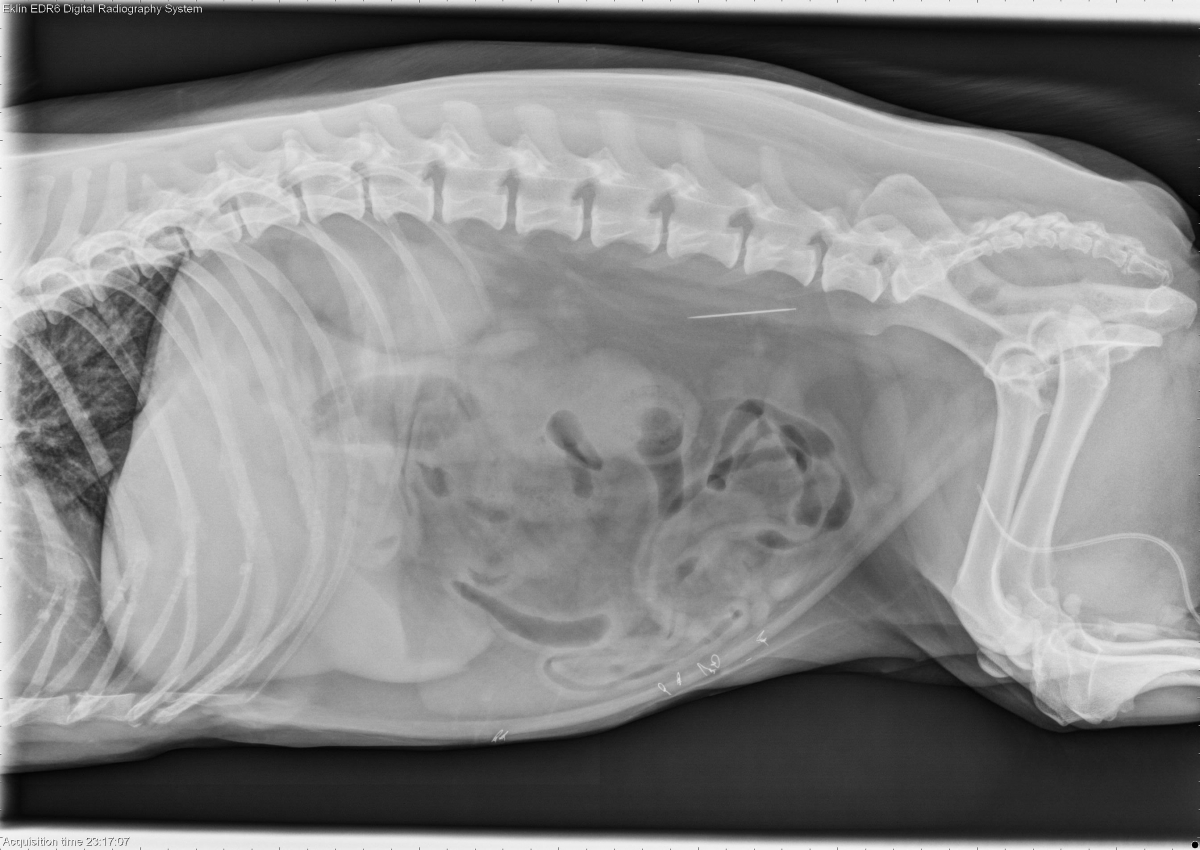

Today’s case is a 10 year old female neutered Corgi with several days of vomiting and anorexia. What is the most important finding?

R LAT Abdomen

Findings

The liver is mildly enlarged with rounded margins. The stomach is mildly distended with fluid and gas. On the ventrodorsal projections, the duodenum is moderately distended with fluid and gas, with several unusual gas bubbles. There is a soft tissue-gas interface at the caudal duodenal flexure. The remainder of the small intestine is normal in diameter. A metallic sewing needle is present in the retroperitoneal space. No abnormalities are noted in the spleen or urinary tract. Radiopaque sutures are present in the ventral abdominal wall.

Duodenal foreign body (corn cob).

An ultrasound examination was performed to confirm the location of the foreign body. The duodenum was distended with fluid proximal to the clean-shadowing foreign object, and returned to normal diameter distal to it. A laparotomy was performed to remove both the foreign body and the sewing needle. The liver biopsy showed vacuolar hepatopathy.